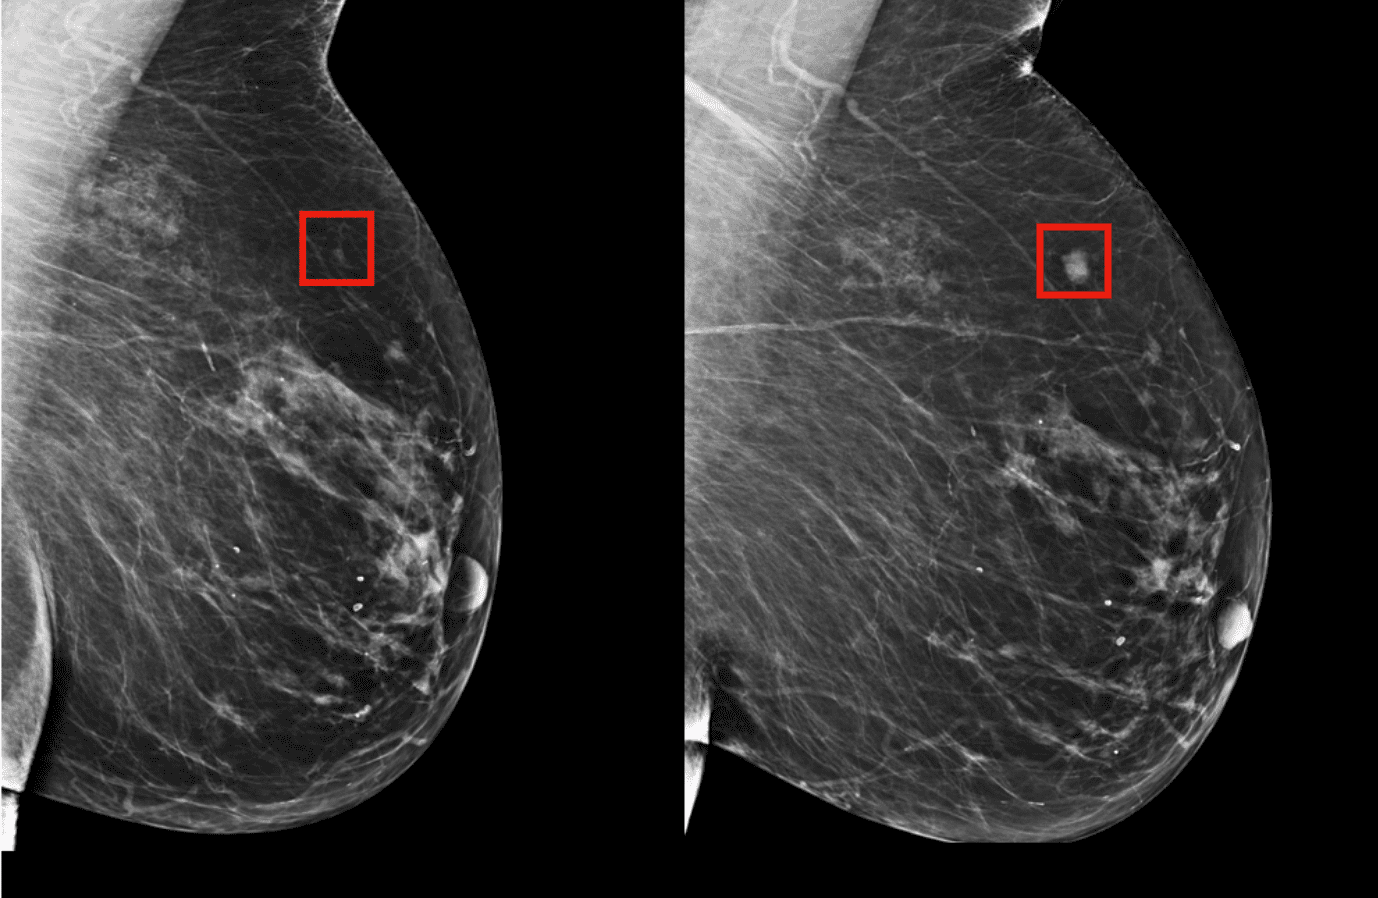

- افراد پرخطر میتوانند غربالگری منظمتر با ماموگرافی یا MRI داشته باشند.

- انجام مرتب غربالگری و ماموگرافی